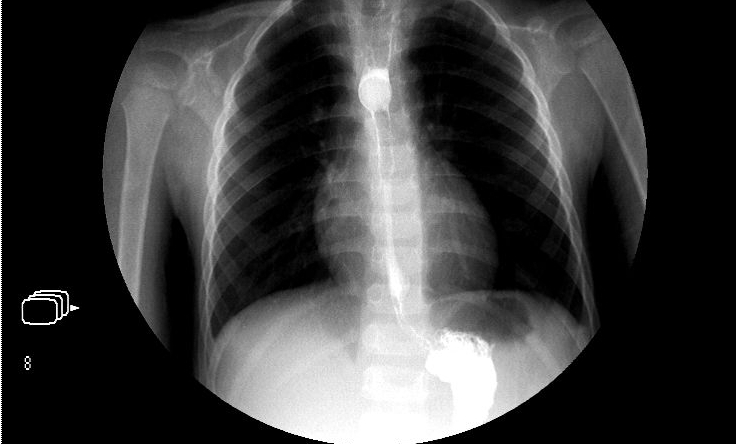

?、傥哥R。通過胃鏡大夫可以直接看到潰瘍,潰瘍是新鮮的還是正在愈合,也就是潰瘍的分期;有無出血、幽門梗阻等并發(fā)癥;潰瘍周圍背景粘膜的改變。更有意義的是可以在病變處取粘膜活檢做病理檢查,特別是對于胃潰瘍的良惡性的鑒別有著重要的意義。此外,還可以做一些關(guān)于幽門螺桿菌的檢查,在另外的問答里我們還會提到該菌與潰瘍的復發(fā)有著非常密切的關(guān)系。所以胃鏡是潰瘍病最佳的確診方法;

?、谏舷涝煊?。目前許多醫(yī)院均采取了雙重對比造影的方法,通過口服較少量的鋇與發(fā)泡劑,使鋇劑與氣體形成對比,更加清晰地勾畫出細小病變浸潤的范圍,但是對反復發(fā)作的十二指腸球潰瘍患者,由于球腔已經(jīng)變形,判斷是否有新的潰瘍出現(xiàn)有一定的困難。